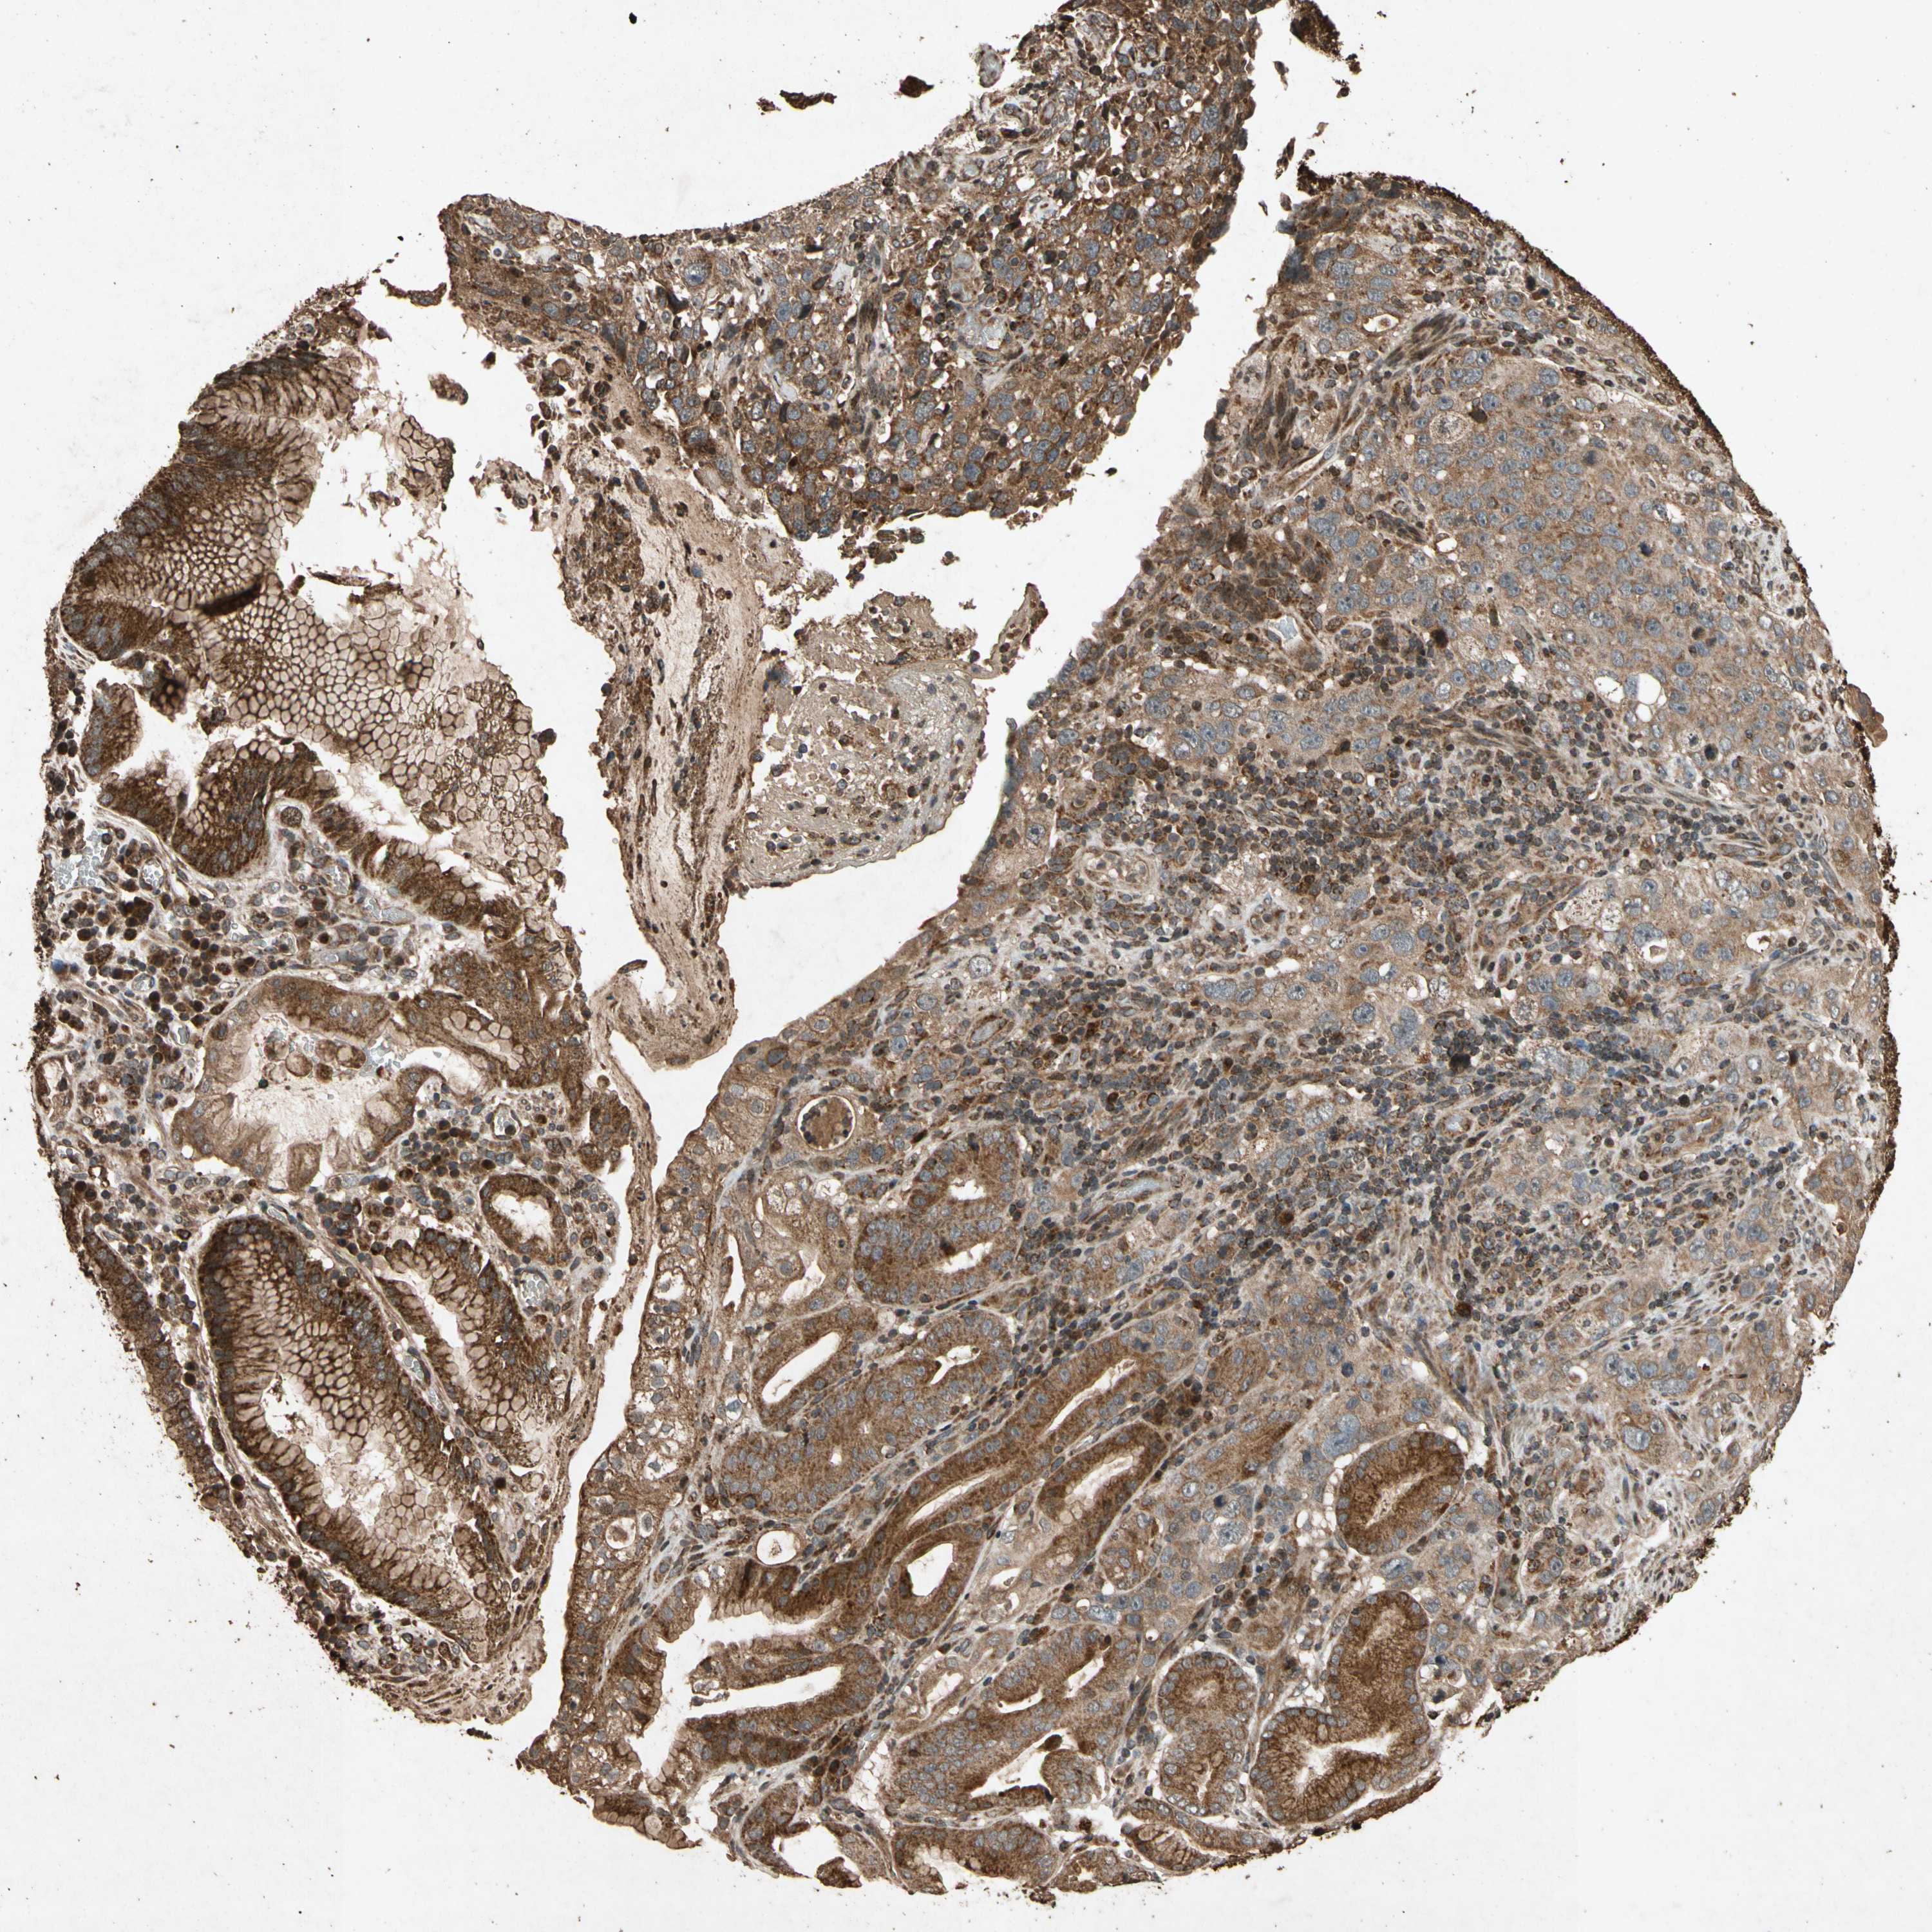

STOMACH CANCER - Protein expressioni

A mouse-over function shows sample information and annotation data. Click on an image to view it in a full screen mode. Samples can be filtered based on level of antibody staining by selecting one or several of the following categories: high, medium, low and not detected. The assay and annotation is described here.

Note that samples used for immunohistochemistry by the Human Protein Atlas do not correspond to samples in the TCGA dataset.

Antibody stainingi

Antibody staining in the annotated cell types in the current human tissue is reported as not detected, low, medium, or high, based on conventional immunohistochemistry profiling in selected tissues. This score is based on the combination of the staining intensity and fraction of stained cells.

Each image is clickable and will lead to virtual microscopy that enables deeper exploration of all samples and also displays staining intensity scores, fraction scores and subcellular localization as well as patient and tissue information for each sample.

Staining

High

Medium

Low

Not detected

Intensity

Strong

Moderate

Weak

Negative

Quantity

>75%

75%-25%

<25%

None

Location

Nuclear

Cytoplasmic/membranous

Cytoplasmic/membranous,nuclear

Adenocarcinoma, NOS